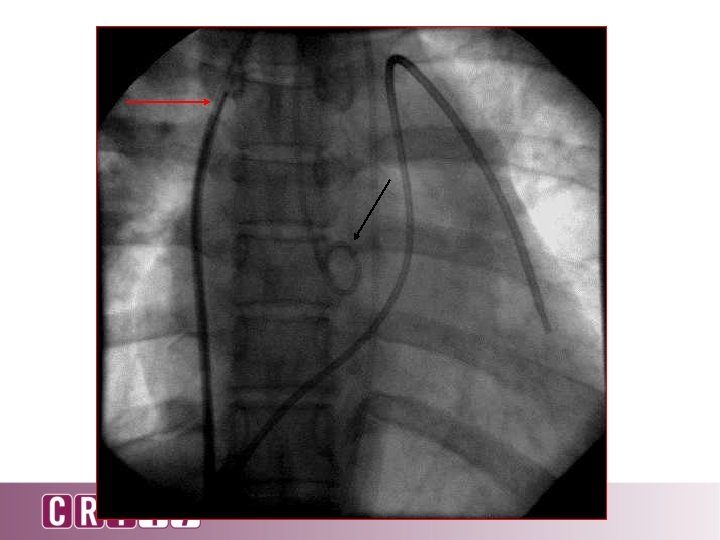

Puncture? No

Puncture? No